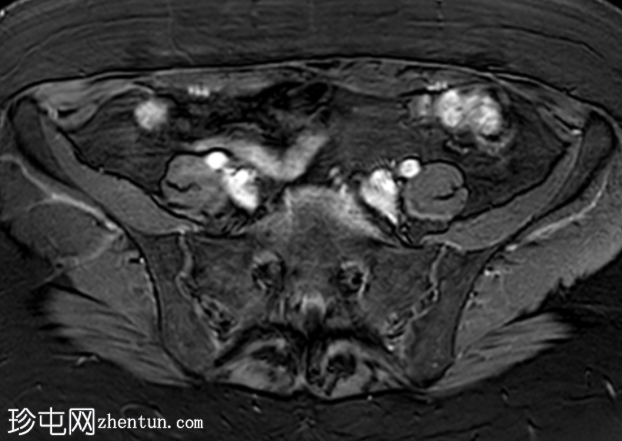

轴位T2加权像

脂肪抑制像

盆腔MRI显示左侧骶前区有两个小囊性病变,位于左侧附件的预期解剖位置。

病变在T2加权像上呈高信号,边界清晰,囊壁轻度增厚,光滑。在T1加权脂肪抑制像上,一个病变内部呈高信号,另一个病变呈低信号。静脉注射对比剂后,可见轻度周边囊壁强化,未见强化的实性成分。

未见扩散受限。病灶与邻近盆腔血管关系密切,无周围炎症改变、盆腔淋巴结肿大或游离液体的证据。